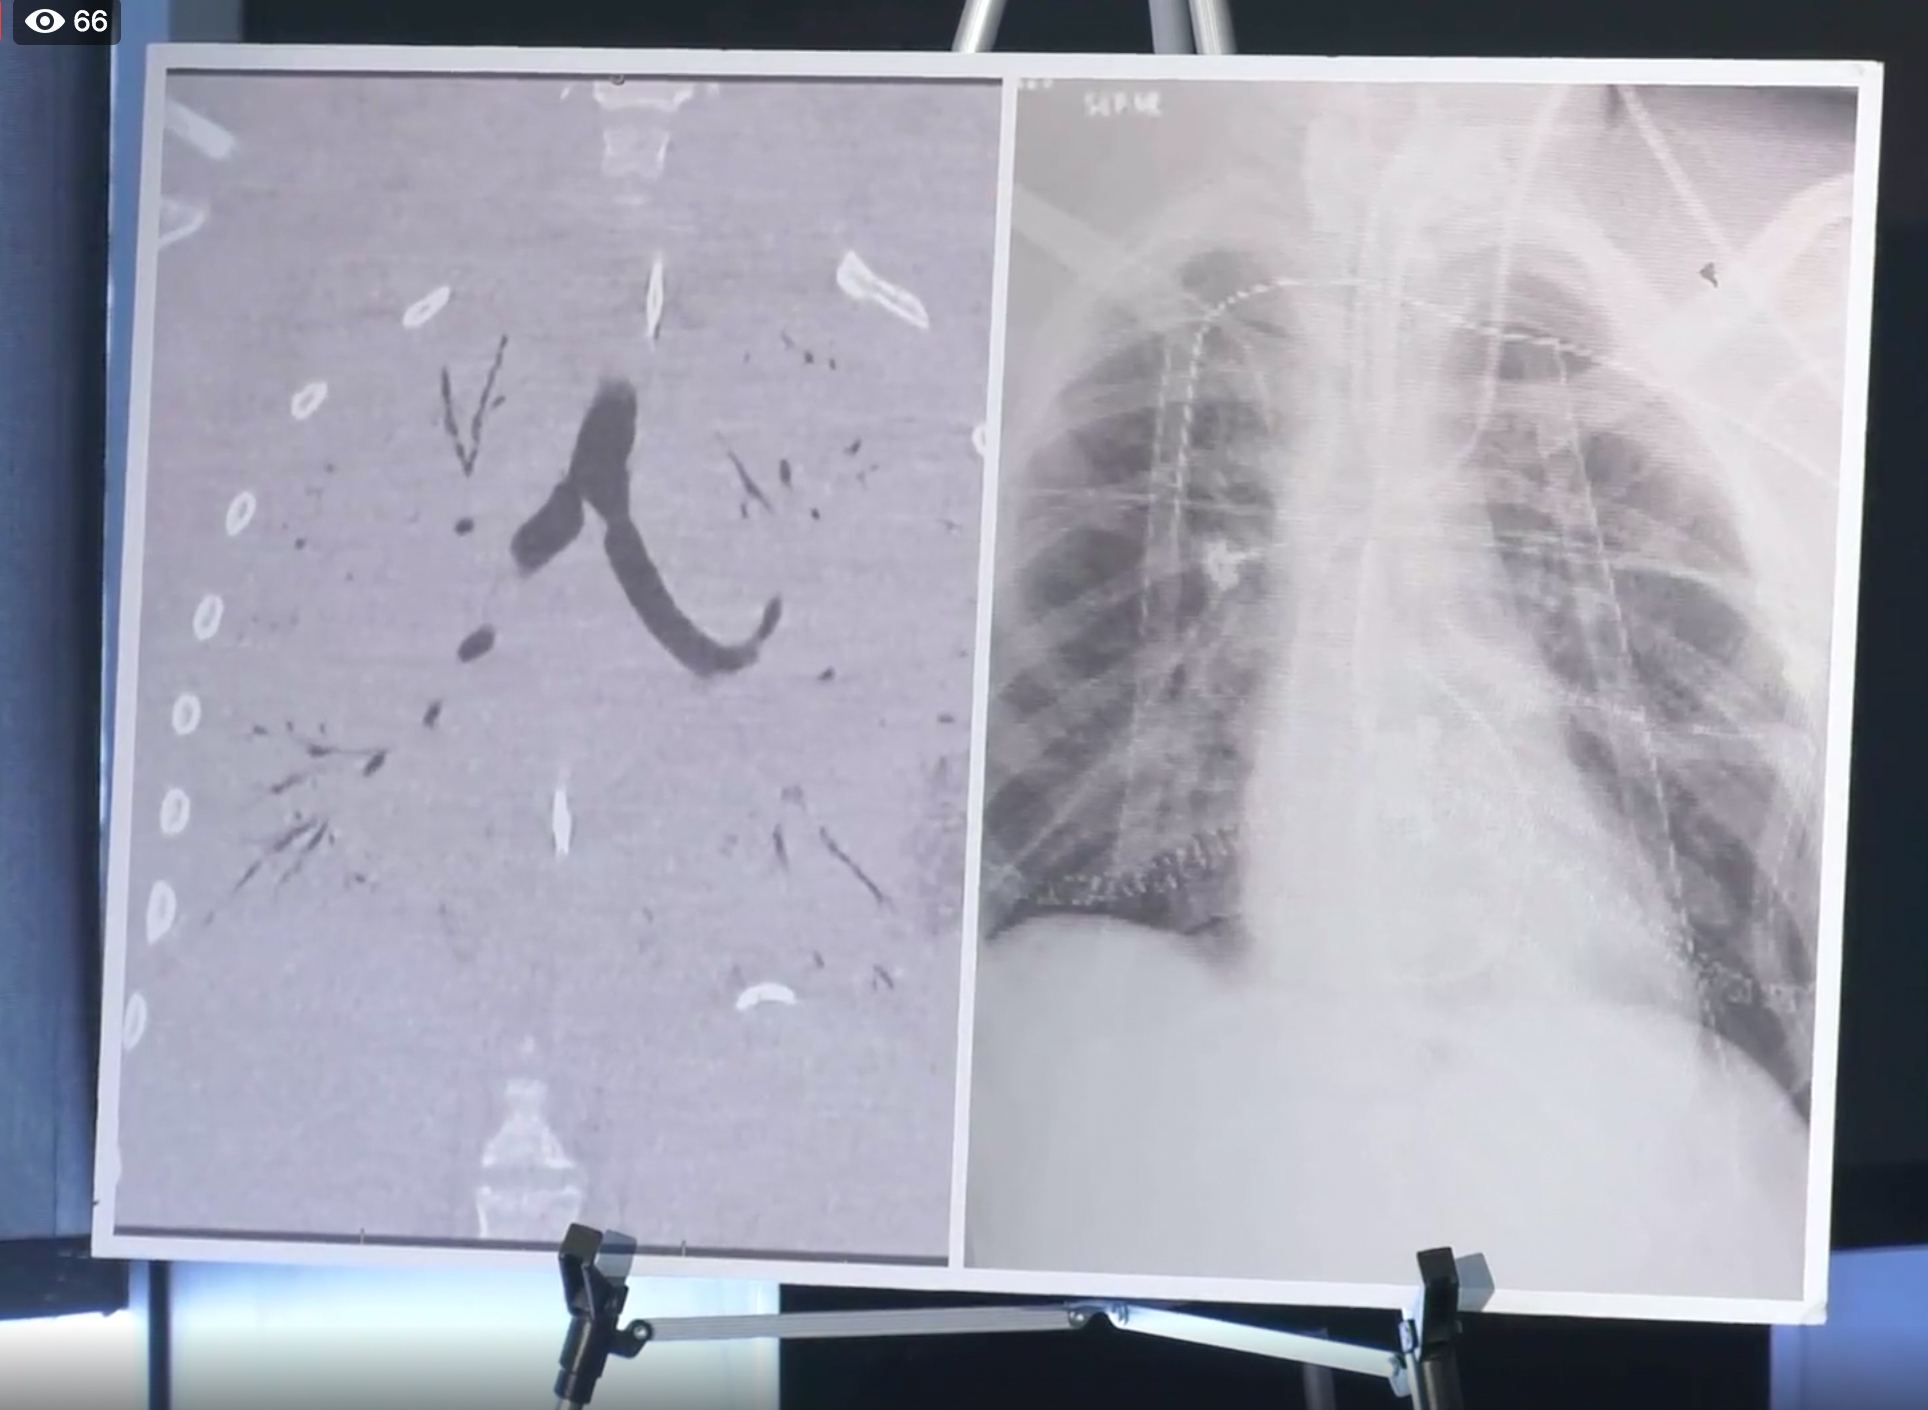

Влияние вейпа на легкие: Фотографии и исследования

Раздел: Визуальный дайджест